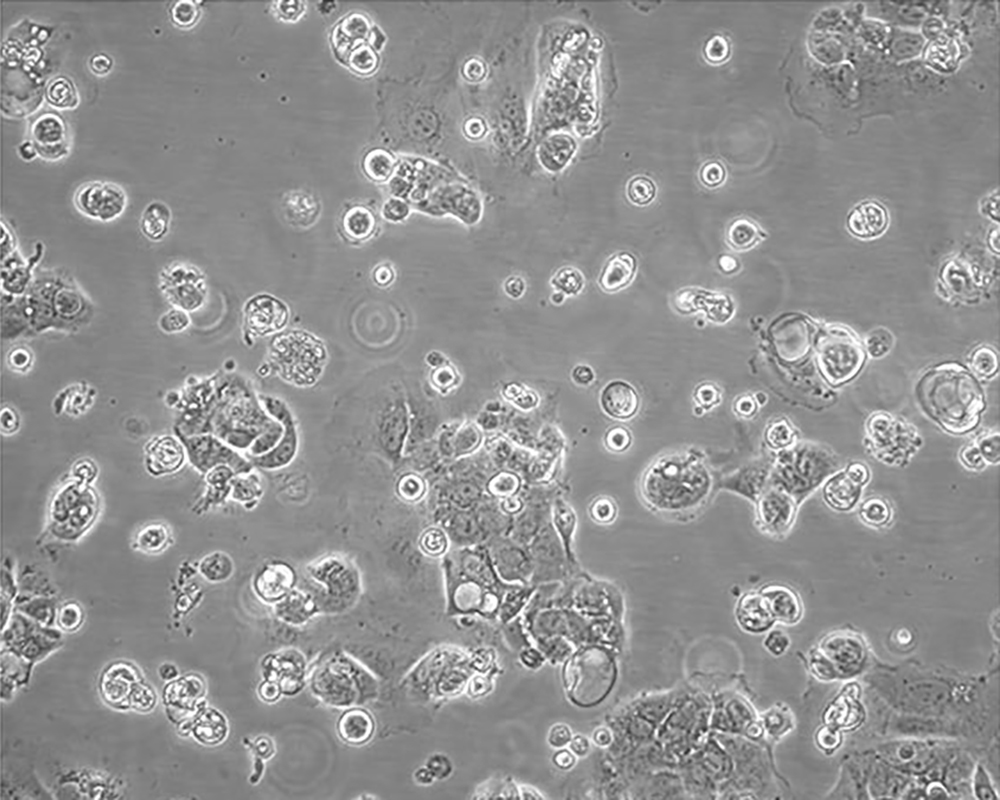

產品名稱 Caco-2

中文名稱 人結直腸腺癌細胞

生長特性 adherent

形態特征 epithelial

細胞描述 Upon reaching confluence, the cells express characteristics of enterocytic differentiation. Ref Caco-2 cells express retinoic acid binding protein I and retinol binding protein Ⅱ.